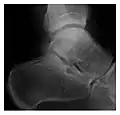

The greater tuberosity of the humerus is also an illustrative location of occult fractures. The osseous injury may follow seizures, glenohumeral dislocation, forced abduction, or direct impaction. They are commonly discovered on MRI in symptomatic patients with suspicion of rotator cuff tear. Coronal images are best suited for detection. They appear as crescentic oblique lines surrounded by a bone marrow edema pattern (Figure 5). The rotator cuff must be inspected since associated ligamentous lesions are common. In the ankle, malleoli and tarsal bones should be checked carefully for any cortical disruptions and radiolucent lines that may reveal a fracture. Awareness of the exact location of the pain will help direct the attention of the interpreter when searching for very subtle signs of fracture (Figure 6).[1]

a

b

Figure 6: Subtle anterior talar fracture in a 39-year-old man presenting with ankle pain after a fall. (a) Anteroposterior radiograph shows a subtle oblique radiolucent line through the talus (white arrows). (b) Sagittal CT reformation confirms the presence of an anterior talar fracture with cortical offset (black arrow). Avulsion fractures, which consist of a detached bone fragment resulting from a ligament or tendon pulling away from the bone, may also present with subtle radiographic signs. Tiny osseous fragments near the presumed attachment site of a ligament suggest this diagnosis. Common sites are the lateral tibial plateau (the Segond fracture), the spinal tuberosity of the tibia resulting from anterior cruciate ligament avulsion, and the ischial tuberosity.[1]